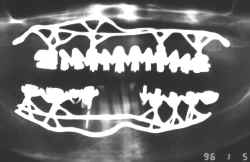

Implantes Dentários Justa Ósseos

Cirurgia Realizada pelos Tenentes Irmãos Petti e Cols.

Unidade de Odontologia do HGEB - MEx Brasília DF

Este caso configura debilidade permanente de função de

acordo com o Código Penal Brasileiro (CP art 129),

sendo que o profissional responsável pelo ocorrido pode ser acionado civilmente de acordo

com o Código Civil Brasileiro (CC 1545), e por

inúmeros artigos do Código de Ética Odontológica.